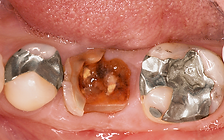

更多单颗后牙缺失 病例 3

36 y M, pain, root fracture 24 with endo RCT before. 5 weeks of soft tissue healing for early implant surgery, with bone graft. 4 months after surgery the tooth was restored. 1.5 y follow up perfect.